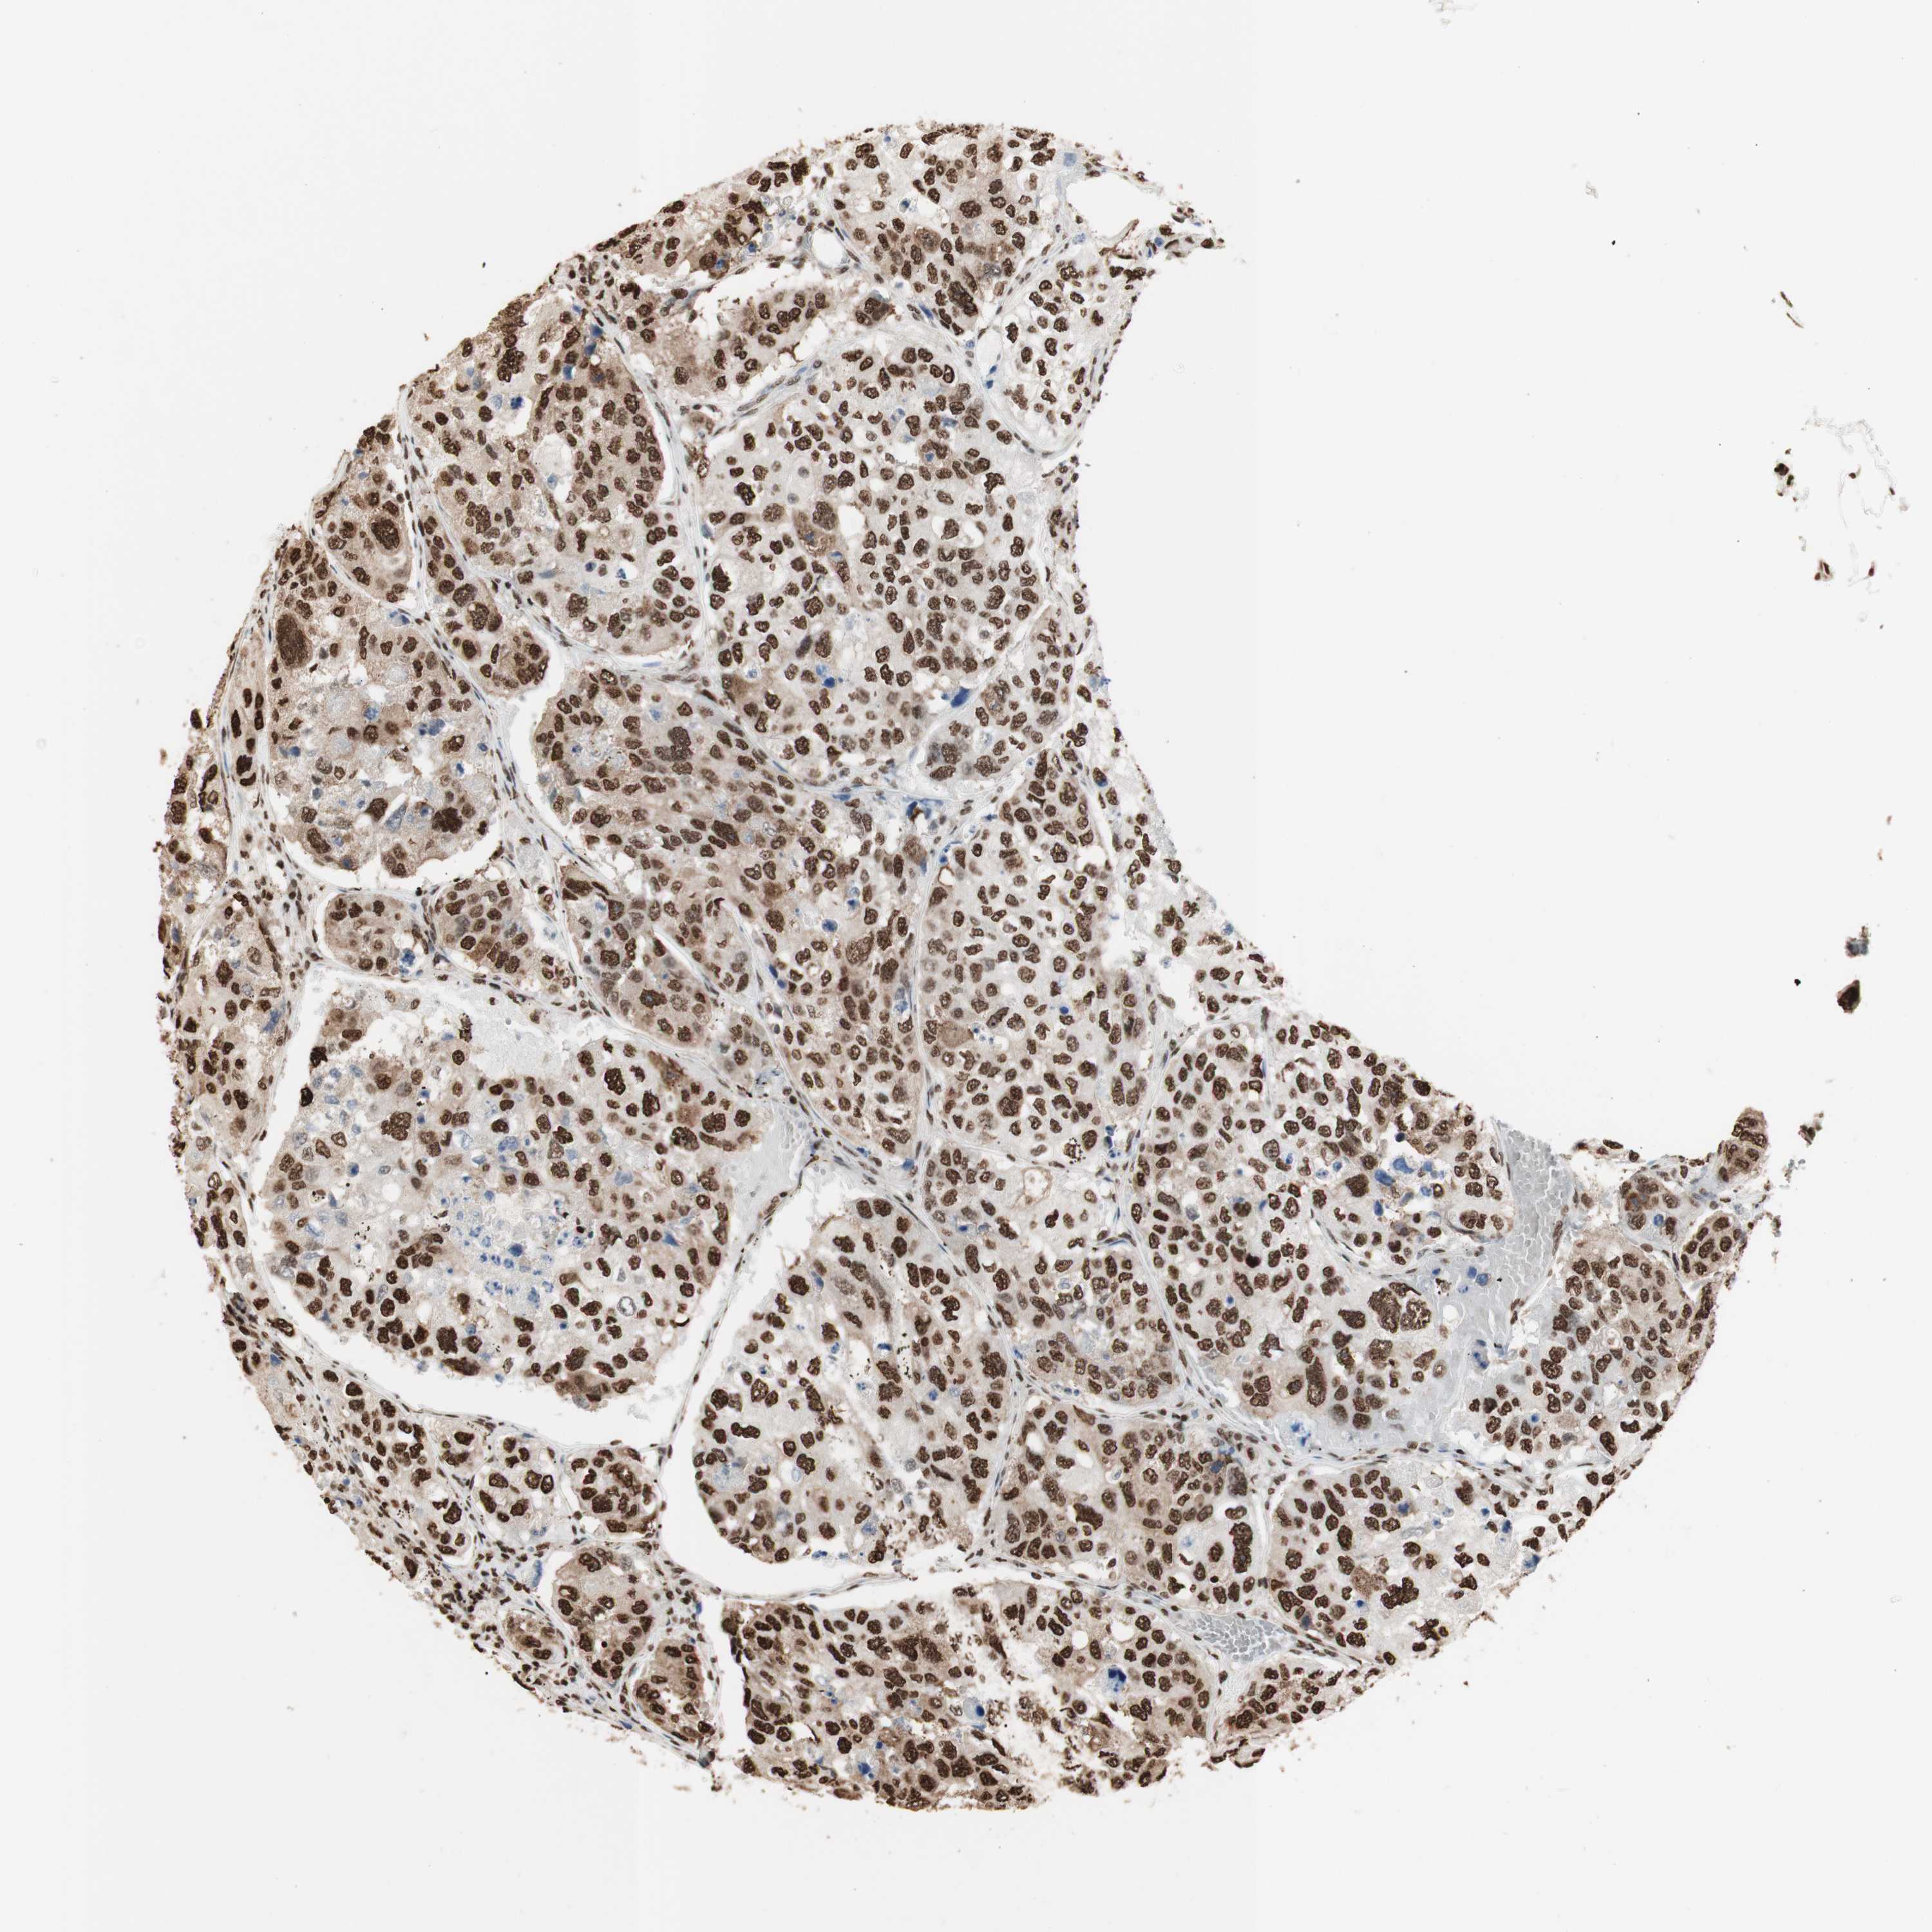

UROTHELIAL CANCER - Protein expressioni

A mouse-over function shows sample information and annotation data. Click on an image to view it in a full screen mode. Samples can be filtered based on level of antibody staining by selecting one or several of the following categories: high, medium, low and not detected. The assay and annotation is described here.

Note that samples used for immunohistochemistry by the Human Protein Atlas do not correspond to samples in the TCGA dataset.

Antibody stainingi

Antibody staining in the annotated cell types in the current human tissue is reported as not detected, low, medium, or high, based on conventional immunohistochemistry profiling in selected tissues. This score is based on the combination of the staining intensity and fraction of stained cells.

Each image is clickable and will lead to virtual microscopy that enables deeper exploration of all samples and also displays staining intensity scores, fraction scores and subcellular localization as well as patient and tissue information for each sample.

Antibody HPA001666

Antibody CAB012403

Staining

High

Medium

Low

Not detected

Intensity

Strong

Moderate

Weak

Negative

Quantity

>75%

75%-25%

<25%

None

Location

Nuclear

Cytoplasmic/membranous

Cytoplasmic/membranous,nuclear

Urothelial carcinoma, High grade

Urothelial carcinoma, Low grade

Adenocarcinoma, NOS